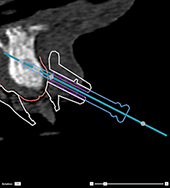

Correct inclination and depth of

anchor pins

To stabilize the surgical

template for implant insertion, anchor pins can be placed at strategic

positions. Their inclination

and depth are crucial.

The anchor pins can

also serve as lip retractors during surgery. Anchor pins spread too widely

within the arch could negatively affect mouth opening. A short-shaft version

of the anchor pin is available to mitigate this effect. Nevertheless,

the anchor pins should be planned so as to offer good access and should

not interfere with the implant sites.